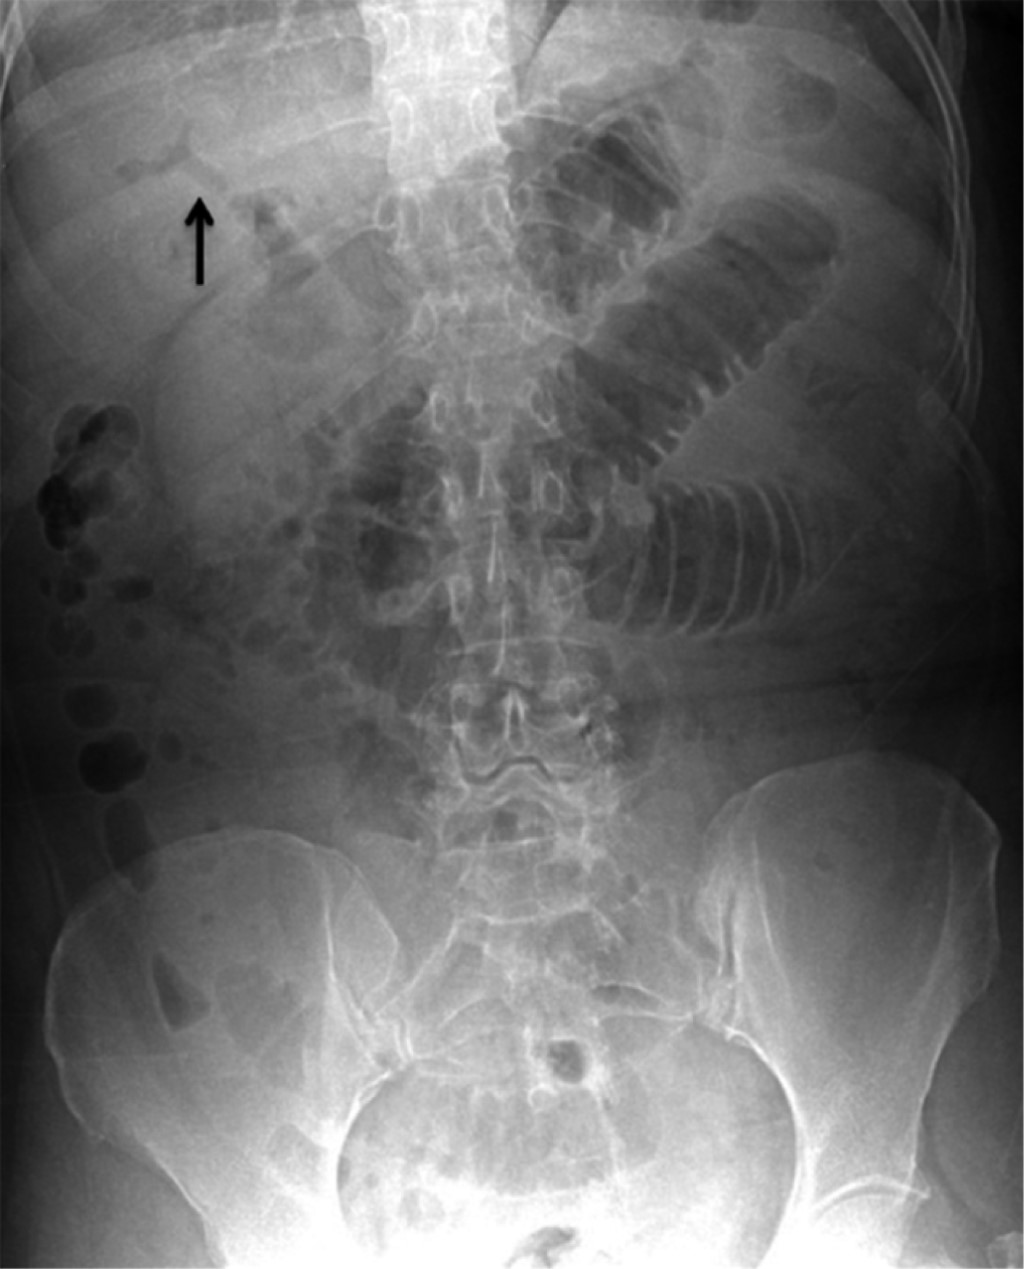

This is the case of a 59-year-old female patient with a history of a stroke event five years ago, type 2 diabetes under control with oral hypoglycemic agents (metformin 850 mg every 12 hours and glibenclamide 5 mg every 24 hours), hiatal hernia and ischemic heart disease under control. She also took acetylsalicylic acid 100 mg orally every 24 hours and atorvastatin 40 mg orally every 24 hours. Her condition began with nausea and vomiting of brown gastrointestinal contents, which leaded to intolerance to the oral route accompanied by pain in the epigastrium zone and referred in intensity of 7/10. She self-medicated with antispasmodics and nonsteroidal anti-inflammatory drugs (NSAIDs), with partial improvement; 48 hours after the onset of symptoms, the intensity of pain increased and she presented abdominal distension, as well as inability to pass gases through the rectum. On admission to the emergency department, the patient was found to be dehydrated, with distended abdomen, painful on superficial palpation and metallic noises on auscultation. A gastric tube was placed, and the aspirated liquid was fecaloid in appearance. Biochemically she had acute renal failure, hydro electrolyte imbalance and metabolic acidosis lab results. Radiographically, there were dilated small bowel loops, pneumobilia (Figure 1) and evidence of intestinal occlusion. In view of this, a laparoscopic surgical exploration was decided which showed dilatation of small bowel loops up to a segment of ileum, located 150 cm from the ileocecal valve, where a protrusion was observed that marked the end of the intestinal dilatation and that corresponded to a 3.5 cm interlocked biliary stone. An enterotomy with stone extraction were performed. The closure was in one plane, with continuous suture with 2-0 Prolene (Figure 2). During the intraoperative period, the patient had hemodynamic instability, so it was necessary to start support with norepinephrine (16 mg in 250 ml of 0.9% saline solution) at a rate of 8 ml/h, dose that was decreased until completely discontinued after 48 hours. Subsequently, she evolved favorably, being discharged on the fifth day while maintaining hemodynamic stability, tolerating the oral route and with no data of systemic inflammatory response. Currently, one year after surgery, she continues to be seen as an outpatient with no complications related to the surgical event.

Radiographic findings in a simple abdominal projection include: pneumobilia, evidence of intestinal obstruction, an image suggestive of a stone in intestinal loops, and changes in the location of the stone as was visualized in a previous radiograph.9-13 The use of computed tomography scan is an important diagnostic support since it has a diagnostic sensitivity, specificity, and accuracy of 93, 100 and 99%, respectively, as has been reported.13 Initial treatment requires IV solution administration, as these patients usually present with dehydration. The laparoscopic surgical approach offers more advantages compared to open surgery; recovery requires less time. However, it represents a technical challenge, especially when the intestinal loops are edematous and dilated.14 In our case, we preferred the laparoscopic approach over the open approach because of the advantages that minimally invasive surgery offers. The patient did not present complications related to the surgical event. There is controversy regarding the management of bilioenteric fistula. On the one hand, only enterotomy, removal of the stone and primary closure is preferred, and on the other, in addition to the above, dismantling of the fistula and cholecystectomy are performed.8 It has been reported that elderly patients with multiple comorbidities represent a real challenge, since there is a considerable increase in leakage, both intestinal and biliary, when performing all the procedures described in a single surgery.15 In our case, we decided to perform only enterotomy, removal of the stone and primary closure due to the patient's condition at the time of admission to the operating room and due to the intraoperative hemodynamic instability. We made the decision to resolve the emergency.

Figure 1